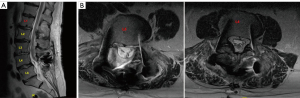

A 71-year-old man with a past medical history of hypertrophic obstructive cardiomyopathy (prior septal myomectomy 2018), chronic obstructive pulmonary disease (COPD), hypertension, gastroesophageal reflex disease with Barrett’s esophagus, hyperlipidemia presented for low back pain with neurogenic claudication and radicular symptoms. Preoperative imaging demonstrated grade 1 spondylolisthesis at L4/5 and right greater than left L4/5 lateral recess stenosis and L4 foraminal stenosis. He was considered an appropriate candidate for L4/5 Total Posterior Spinal System (TOPS) (Figure 5).

While the patient was being weaned from anesthesia, he was noted to be demonstrating seizure-like convulsions. Propofol was re-initiated with resolution of clinical seizure activity. The patient was taken to emergent noncontrast head CT which demonstrated a right SDH with 7–8-mm midline shift (Figure 6). Neurosurgery was consulted for further management and the patient was loaded with levetiracetam, and was brought to the operating room (OR) with neurosurgery for emergent craniotomy and hematoma evacuation.

A large right hemicraniotomy was performed and the dura was opened sharply, revealing a large acute SDH. Surgicel was applied to bridging veins emptying into sagittal sinus which were medial edge of the hematoma but which did not appear to be actively bleeding. No obvious active source of hematoma was identified, and brain appeared relaxed and pulsatile following hematoma evacuation. Patient’s surgical incision was closed in the standard fashion. The patient was subsequently transferred to the intensive care unit (ICU). Postoperative drain output days 1–3 were 807, 250, and 0 mL. MRI postoperative day 3 demonstrated an area of possible dural deficiency without pseudomeningocele or large fluid collection over the laminectomy bed (Figure 7). He was placed on flat bedrest, and his drain was placed to gravity and clamped. He was extubated on postoperative day 4 and his subfascial drain was unclamped, was pulled and oversewn.